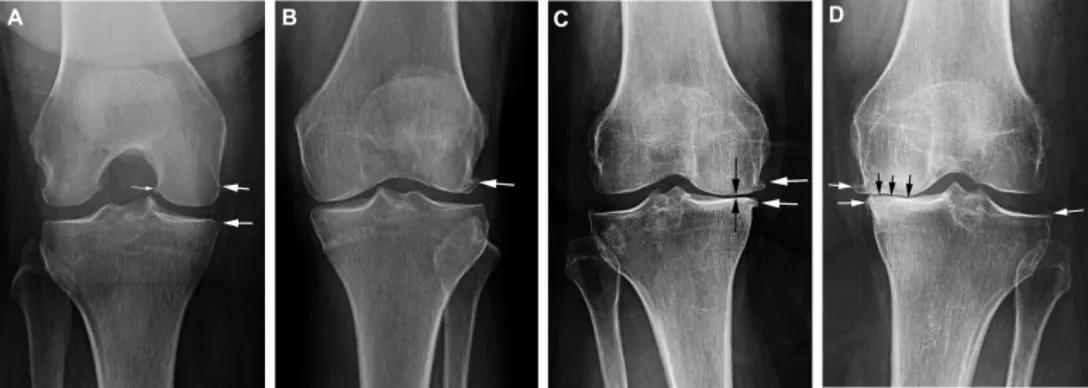

臨床上我們依據 X 光片(Kellgren-Lawrence 分級)將退化程度分為四級:

- 第一級 (Grade 1): 疑似有骨刺,關節間隙正常。症狀輕微,偶爾痠痛。

- 第二級 (Grade 2): 看到明顯骨刺,關節間隙輕微變窄。上下樓梯開始無力。(這是保養的黃金期!)

- 第三級 (Grade 3): 骨刺多,關節間隙明顯變窄(軟骨磨掉一半)。蹲下困難,走久會痛。

- 第四級 (Grade 4): 關節間隙消失(骨頭磨骨頭),骨頭變形。寸步難行,可能需要考慮人工關節置換。